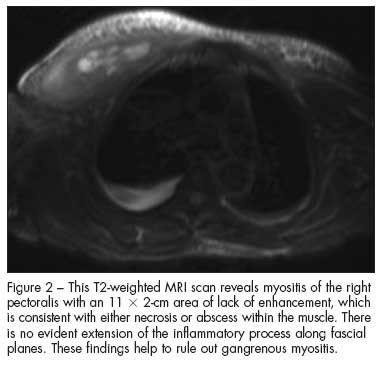

The CT scan of the chest shows increased subcutaneous stranding of the right breast and enlargement of the pectoralis major, with shotty axillary lymphadenopathy (Figure 1). The MRI scan demonstrates myositis of the right pectoralis with an 11 x 2-cm area of lack of enhancement, which is consistent with either necrosis or abscess within the muscle (Figure 2).

Diabetic muscle infarction (choice A) is a noninfectious complication of chronic uncontrolled diabetes. As with the other causes of myositis, diabetic muscle infarction produces isolated muscle inflammation that results in pain, swelling, and erythema. MRI typically demonstrates an area of lack of enhancement similar to the one seen on this patient’s MRI scan. However, fever, leukocytosis, and abscess are not characteristic of diabetic muscle infarction.